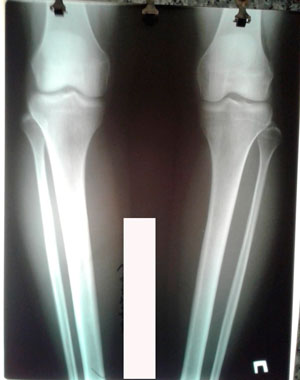

Исходник - 38 лет.

Дата операции - 16.06.2020

до круток

Дата снятия аппаратов - 13.10.2020